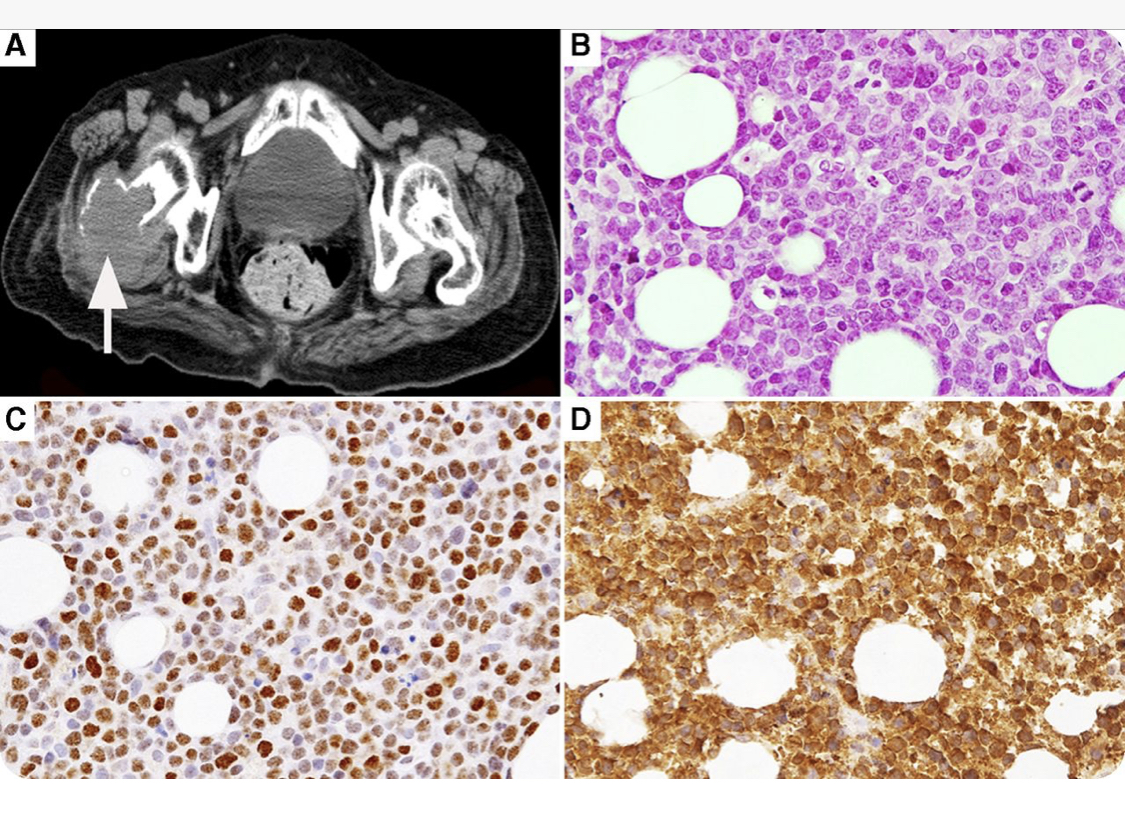

?hypercalcemia ?PTHrP ?CyclinD3 ?Blastoid MCL https://t.co/30HvnG0pVN